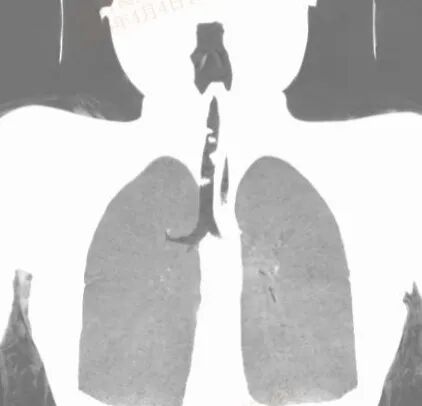

术前颈胸部CT三维重建

气管内多发软组织密度影,气道重度梗阻